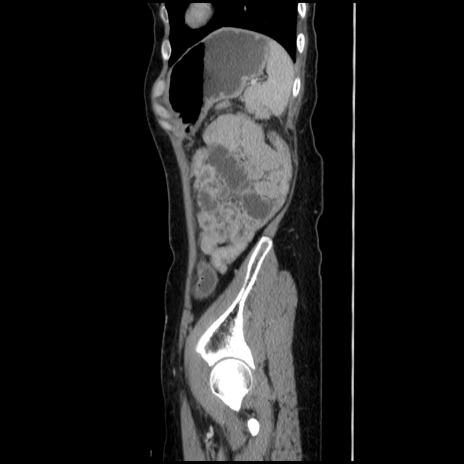

症例32(矢状断像)

【症例】40歳代 女性

【主訴】上腹部痛、嘔気・嘔吐

【現病歴】約9時間前頃から急に上腹部痛、嘔気、嘔吐が出現。改善しないため救急要請。

【既往歴】子宮頚癌(広汎子宮全摘術、放射線療法)、腸閉塞

【身体所見】腹部:平坦、軟、腸雑音亢進、上腹部を中心に腹部全体に圧痛あり。

【データ】WBC 8400、CRP 0.03